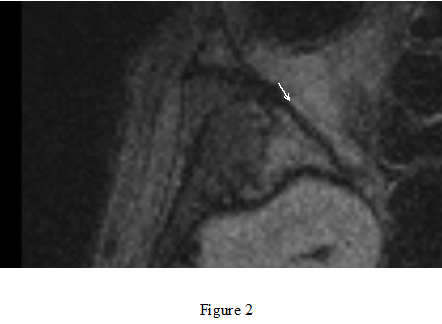

Visualization of endolymphatic hydrops has become available using 3T MRI with contrast agents (Figure 1). We have investigated the existence of endolymphatic hydrop in various ear disorders. We evaluate breakdown of blood-labyrinth barrier, which could be a factor for predicting prognosis of inner ear disturbances (Figure

2). The evaluation is also available to avoid complications following surgeries for cholesteatomas with labyrinthine fistulae.